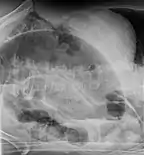

An x-ray of a person with a small bowel volvulus.

Plain X ray of a cecal volvulus